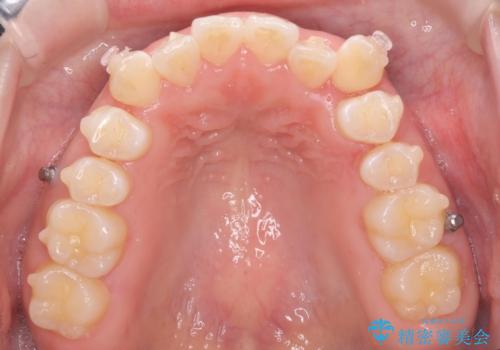

八重歯を非抜歯で マウスピースで治療 奥歯を後ろに下げてすき間を確保

- 八重歯を主訴に来院。

仕事柄ワイヤーが見えるよりはマウスピースで目立たなく歯並びを良くしていきたいとのことでした。

奥歯を後ろに下げてすき間を確保し、八重歯を引っ込めて並べる治療を行いました。

奥歯を後ろに下げるために、矯正用のミニスクリューを使用しています。